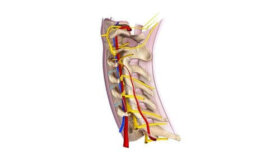

경추 척수신경에 대해 들어본 적이 있는가? 경추 척수신경(Cervical Spinal Nerves)은 척수에서 비롯한 8개의 경추에서 나온 8개의 척수 신경 그룹이다. 이 8개의 경추(C-1에서 C-8)는 두개골의 밑면에서 시작된다. C-1(일반적으로 배근이 없음)을 제외한 모든 경추 척수신경은 피부에 연결되어 있다. 그리고 피절은 경추 척수신경에…